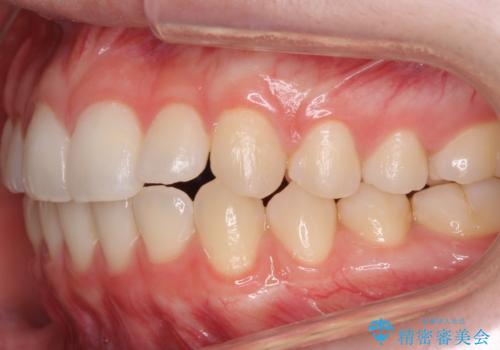

咬んでも向こう側が見える、前歯が閉じない症状でした。また、上の前歯が少し前に出ている状態でした。

上の前歯をわずかに削る処置を行い、後ろに下げながら下の歯となるべく咬むように矯正治療を行いました。